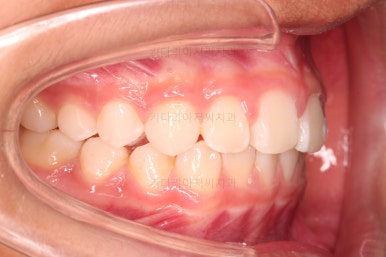

부산소아교정 초진 시 입안의 모습입니다.

윗니가 아랫니보다 많이 앞에 나와있고요.

심지어는 틈새가 벌어지기까지 했습니다.

윗니가 배열 되어있는 U자 형태(그릇 형태)가 아랫니보다 좁은 양상이고요.

이런 앵글씨 2급 부정교합에서는 아랫니가 윗니와 만나기 위해 솟구쳐서 과개교합(아래 앞니가 윗니 뒤쪽으로 깊숙히 올라가 있는 상태)이 나타나기까지 합니다.